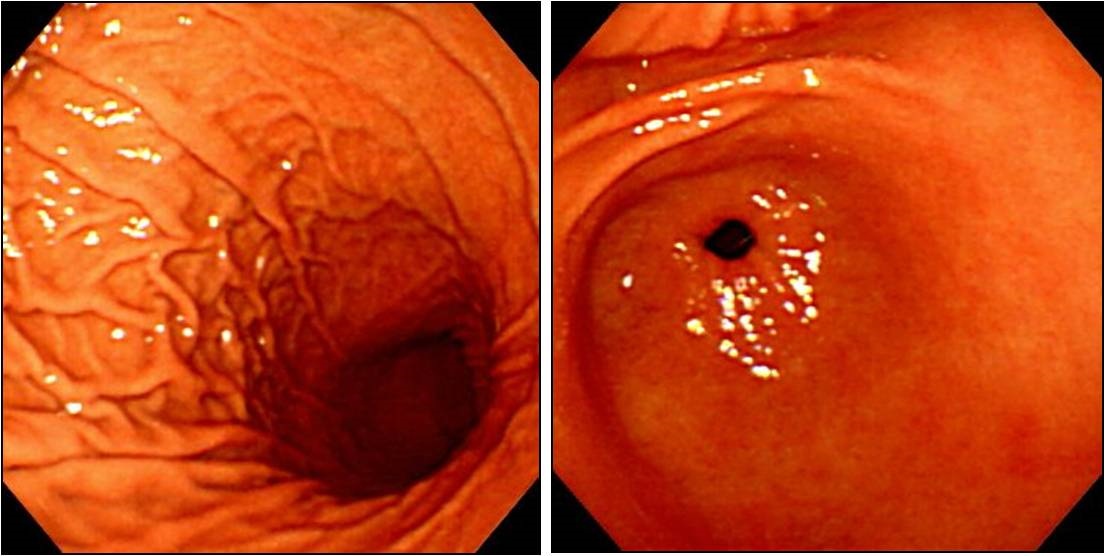

위궤양을 치료받으신 후에도 정기적으로 검진을 받는 것이 필수적입니다. 검진을 통해 궤양의 재발 여부를 체크하고, 적절한 조치를 취할 수 있습니다. 가장 흔히 시행되는 검사는 위내시경을 통한 검사입니다.

내시경을 통해 위의 상태를 직접 확인할 수 있으며, 필요한 경우 생검을 통해 추가적인 진단을 진행할 수 있습니다. 이러한 조치는 위장 질환의 초기 발견과 조기 대응에 중요한 역할을 합니다.